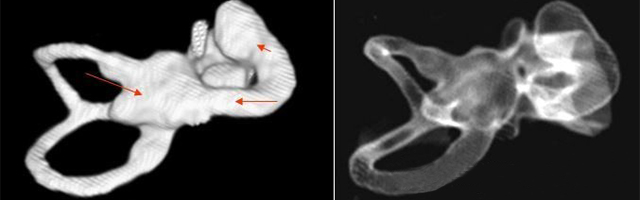

主要根據(jù)聽力學(xué)表現(xiàn)和影像學(xué)檢查。通過(guò)高分辨CT可看到耳蝸畸形。內(nèi)耳MRI顯示膜迷路內(nèi)水充盈,耳蝸扁平,耳蝸第二圈與頂圈間隔缺損,以及半規(guī)管、前庭的畸形。

先天性耳蝸畸形伴前庭和外半規(guī)管發(fā)育不良